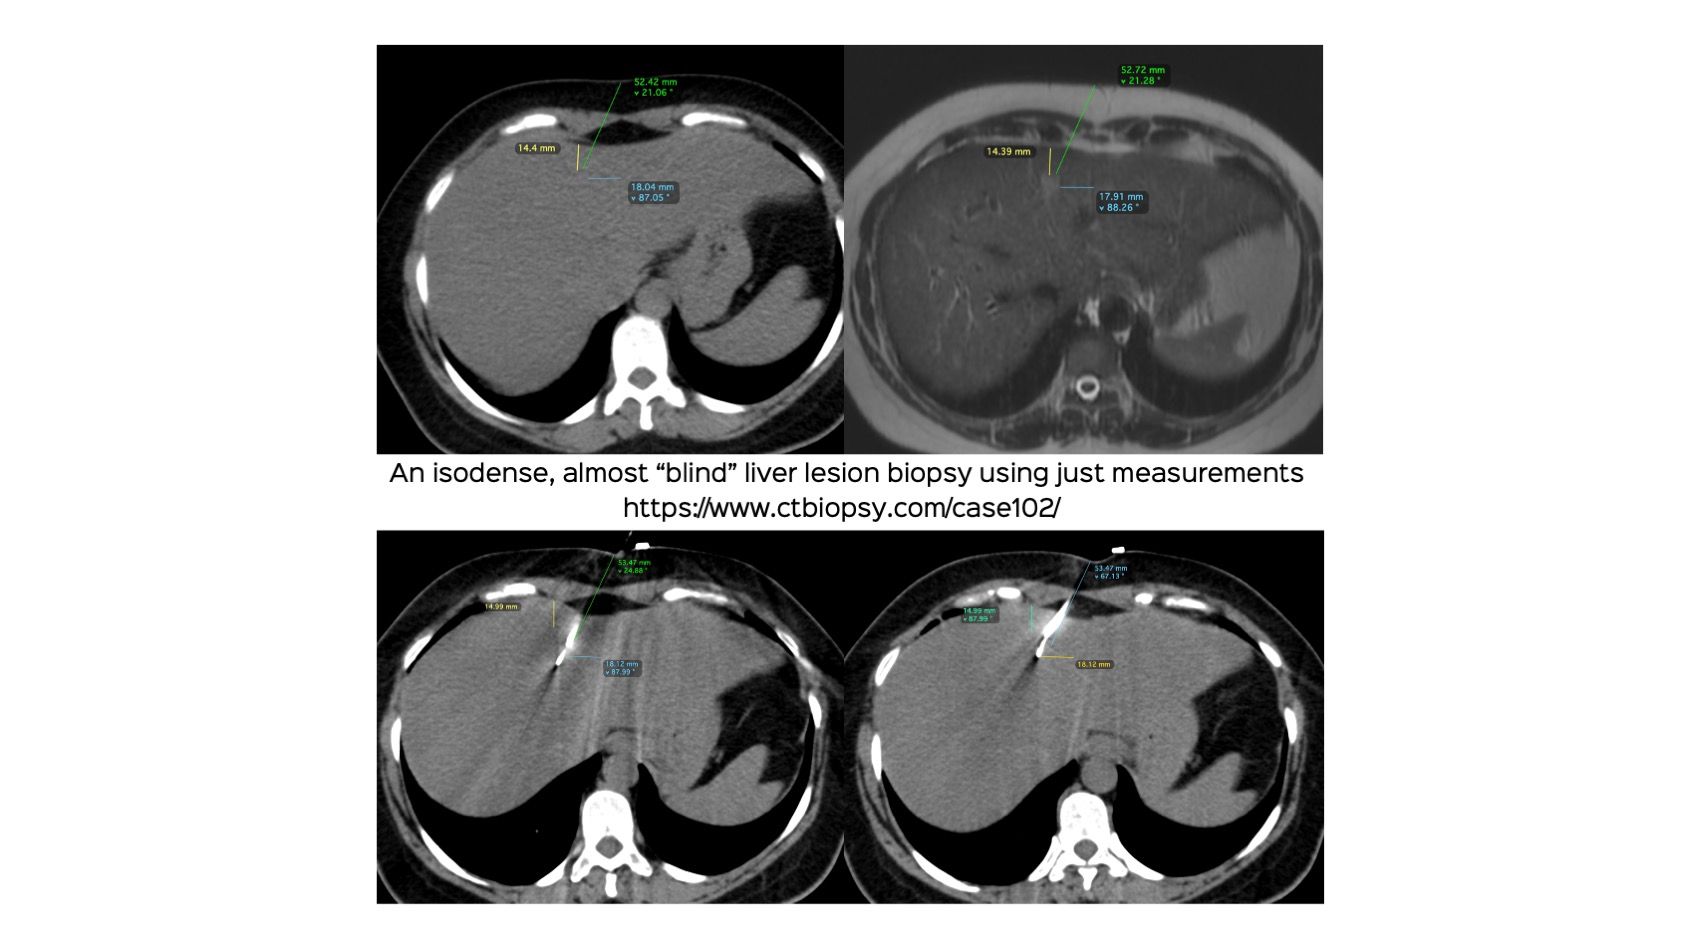

Case 102: Almost Blind Liver Lesion Biopsy using Just Measurements and Feel